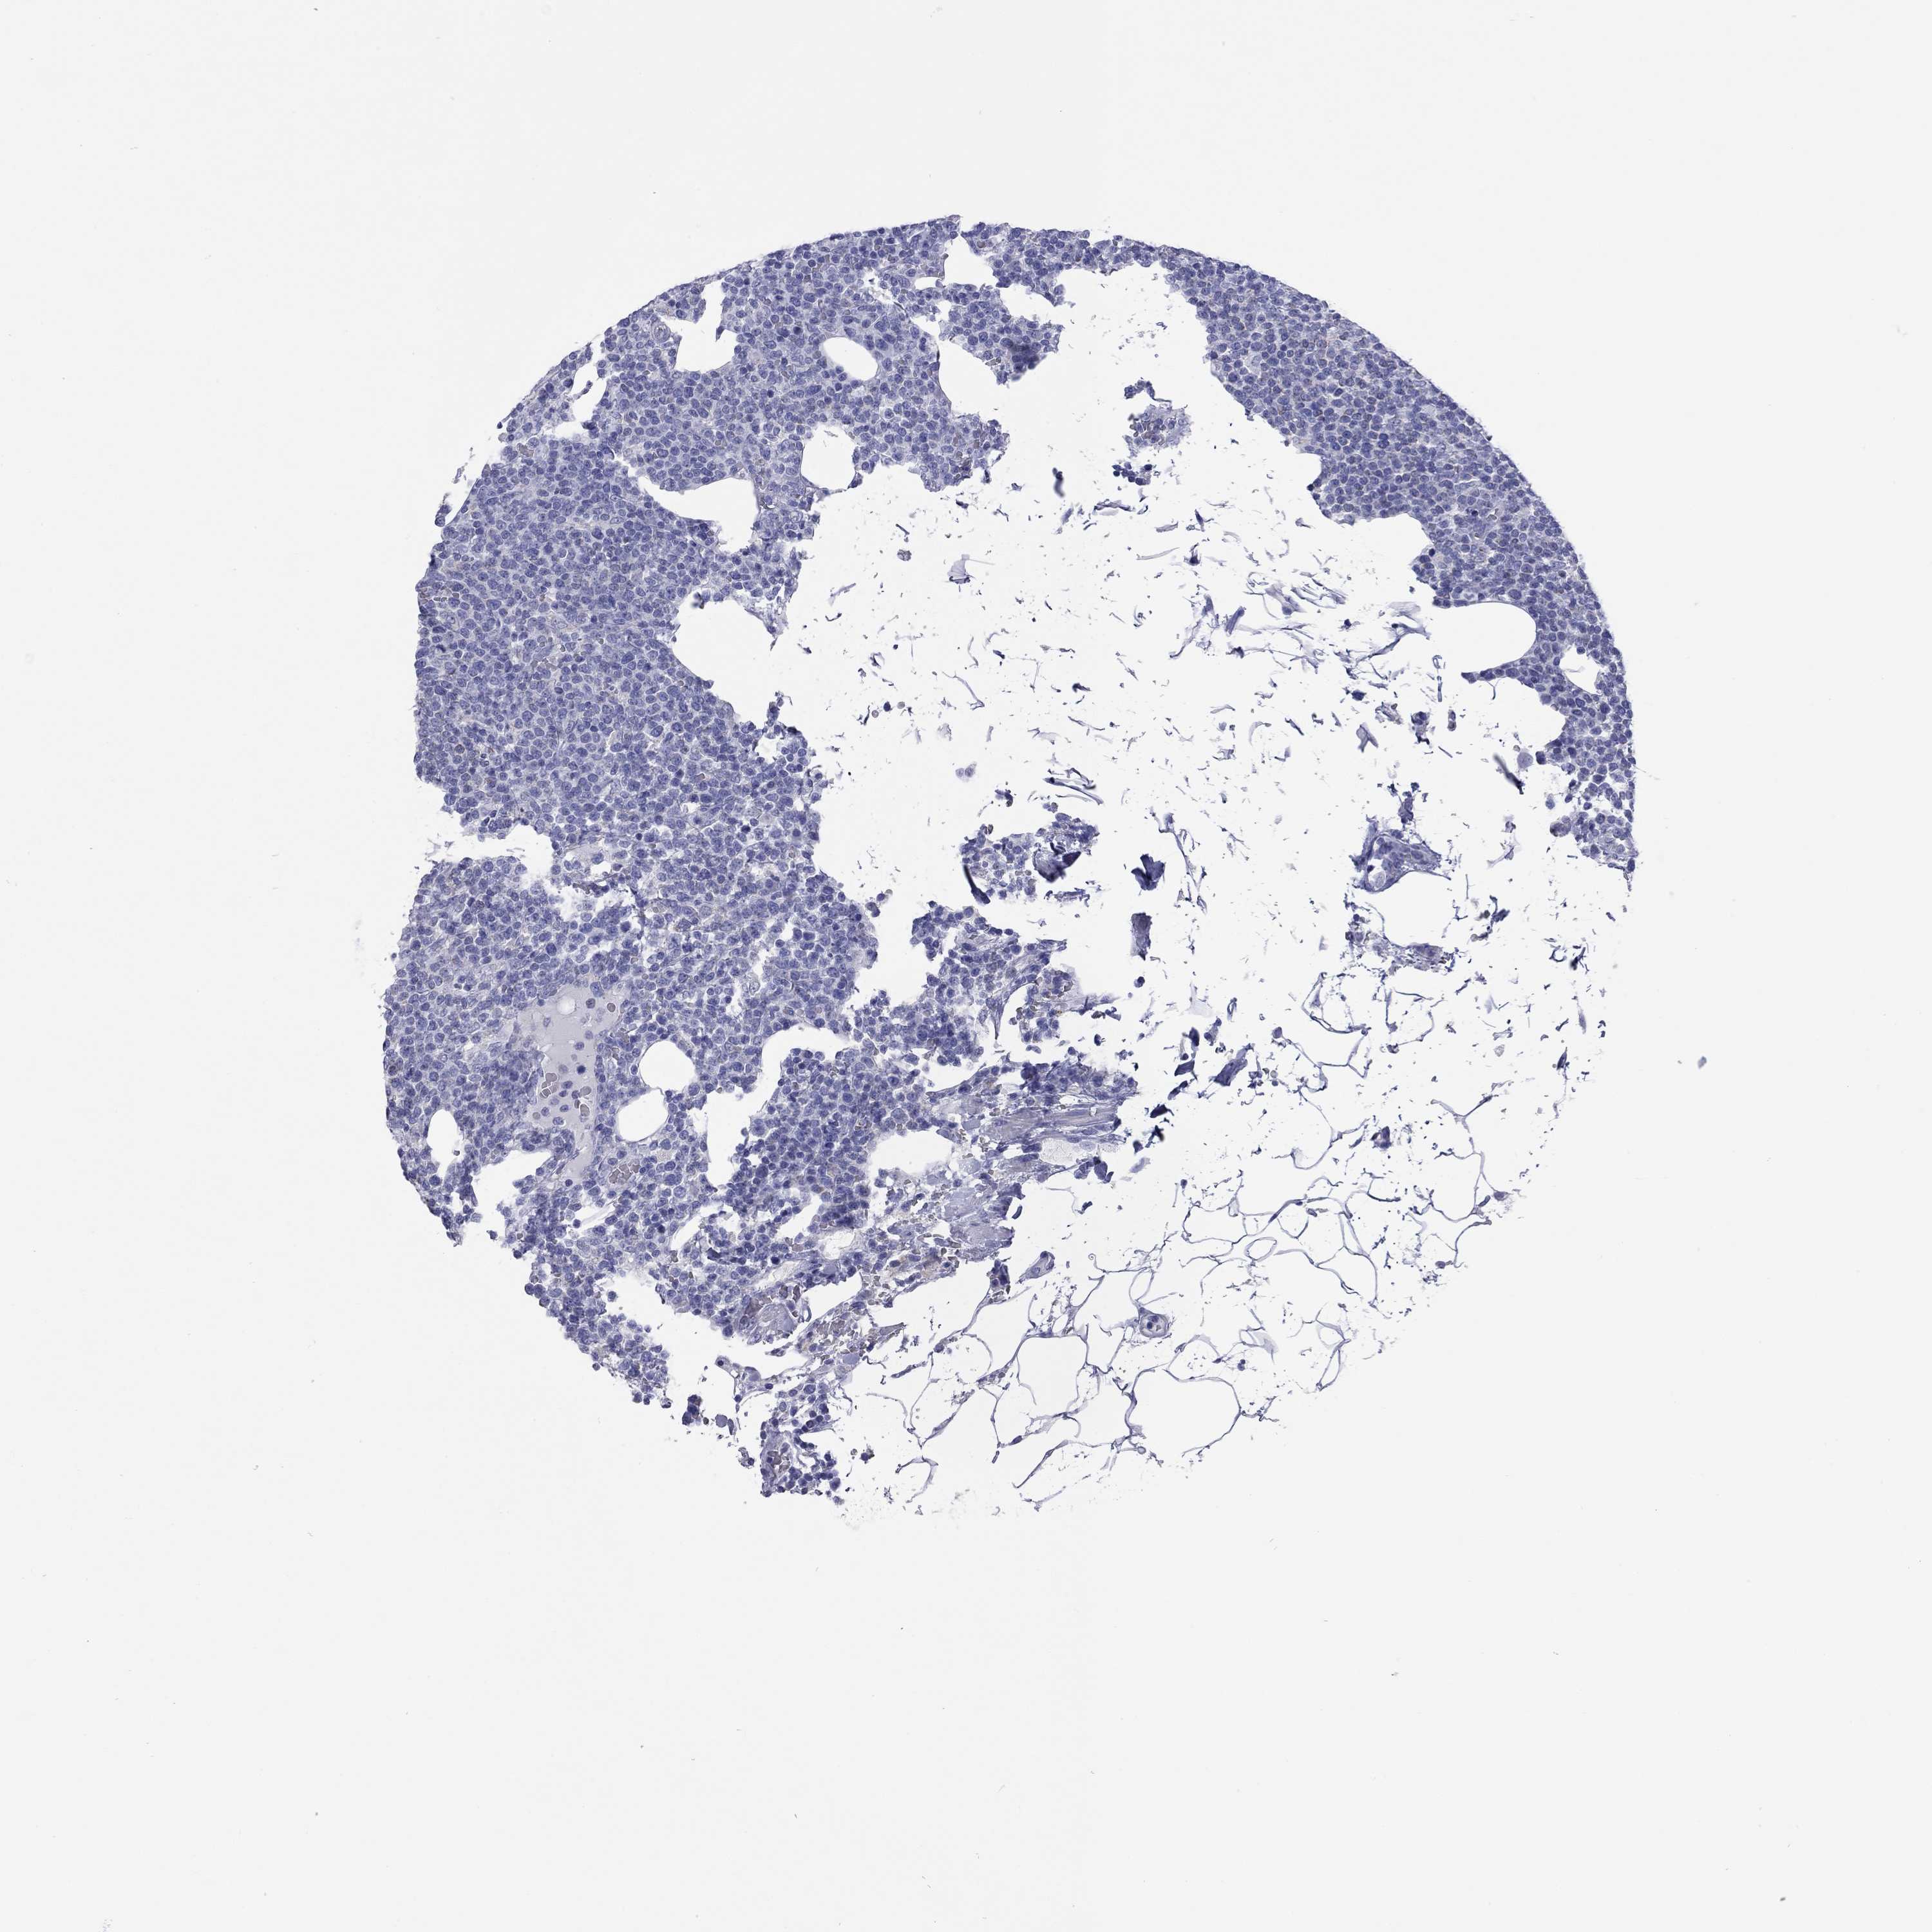

CANCER LYMPHOMA Show tissue menu

LYMPHOMA - Protein expressioni

A mouse-over function shows sample information and annotation data. Click on an image to view it in a full screen mode. Samples can be filtered based on level of antibody staining by selecting one or several of the following categories: high, medium, low and not detected. The assay and annotation is described here.

Each image is clickable and will lead to virtual microscopy that enables deeper exploration of all samples and also displays staining intensity scores, fraction scores and subcellular localization as well as patient and tissue information for each sample.

Antibody HPA062022

Staining

High

Medium

Low

Not detected

Intensity

Strong

Moderate

Weak

Negative

Quantity

>75%

75%-25%

<25%

None

Location

Nuclear

Cytoplasmic/membranous

Cytoplasmic/membranous,nuclear

Malignant lymphoma, non-Hodgkin's type, Low grade

Malignant lymphoma, non-Hodgkin's type, High grade

Hodgkin's disease, NOS